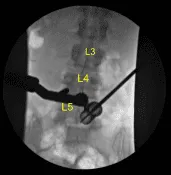

La piel se abrió con un bisturí #15. La hemostasia se obtuvo con Bovie. Se utilizó Bovie para dividir bruscamente la fascia. Se usaban dilatadores secuenciales para acoplar un separador tubular de 16 mm de diámetro x 4 cm que se fijaba rígidamente al armazón de la cama.

El microscopio quirúrgico fue llevado al campo para la microdisección utilizando instrumentos y técnicas microquirúrgicas durante el resto del procedimiento. Se usaron rongeurs de bovie, monopolar e hipofisario para resecar los superyacentes

tejido blando sobre la lámina L5 derecha.

Se utilizó un taladro eléctrico de alta velocidad con irrigación estéril para realizar laminotomía L5 derecha, exponiendo el ligamento flavo, que se desprendió rostral de la lámina ventral con una cureta angulada y se reflejó caudalmente, y luego se resecó de forma fragmentada con rongeurs de Kerrison de 2 y 3 mm que dejaron al descubierto la duramadre intacta.